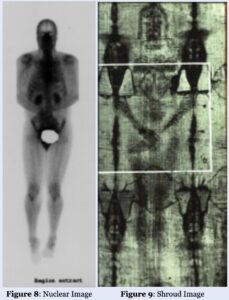

The paper states, “Third we demonstrated that the nature of the emitted radiation is such that it produces an image void of a sharp outline such as that on the Turin Shroud.” See Figures 6 and 7.

Regarding lighting, the paper states, “Fourth we demonstrated that the resulting radiation image is void of any light focus such as the Shroud.”

Various aspects of physiology are similarly apparent. “Sixth, the fact that soft tissues, skeletal information, as well as pathology in these tissues, can all be imaged concomitantly using the nuclear medicine model, demonstrates the parallel to the Shroud where the same is observed.”

This paper is not particularly lengthy; readers are encouraged to look through the original. The body of the paper shows numerous comparisons between nuclear imaging and the image on the TS, as well as correlations with the three-dimensional imaging aspects addressed right before the Corona Discharge section. For the sake of brevity, only a few of the examples are included in this report. The images and image commentary that appear in this section of the report are from the paper.